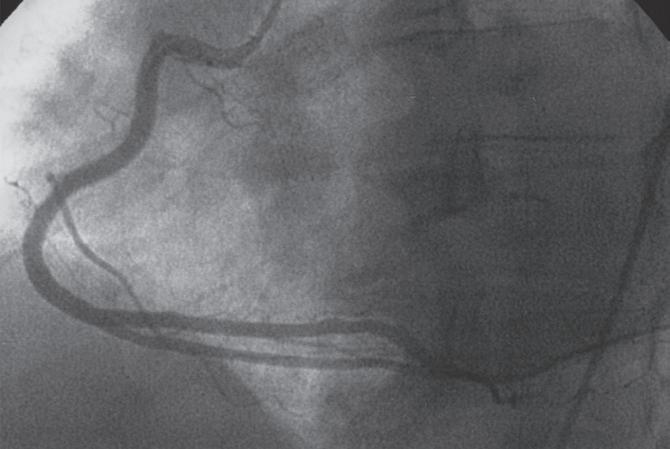

Figura 18.36 – Angiografia da artéria coronária direita. Visualização das diversas colaterais. A. Oblíqua anterior esquerda 45º caudal 15º; B. Oblíqua anterior direita 45º.

Figura 18.37 – Coronariografia da artéria coronária direita (dominante).

Artéria coronária direita

O ostium da artéria coronária direita (CD) tem origem na parte superior e ligeiramente anterior do seio coronário direito, junto à união sino tubular da aorta, ficando, no entanto,